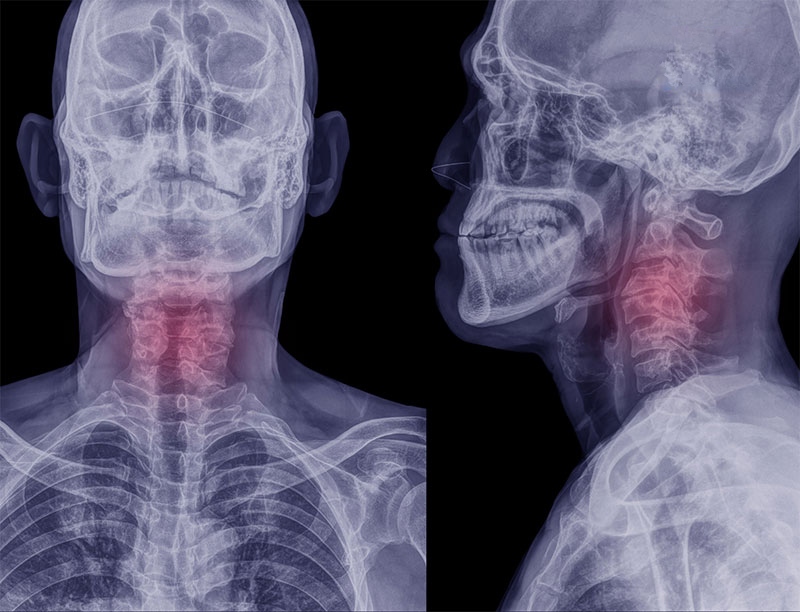

Gai đốt sống cổ: Nguyên nhân, triệu chứng và cách phòng ngừa

Gai đốt sống cổ (Cervical Osteophytes) là sự hình thành của xương nhô ra ở phần giữa các cạnh xương và khớp vùng cột sống cổ, dẫn đến tình trạng đau nhức và để lại nhiều biến chứng nếu không có biện pháp can thiệp kịp thời. Bệnh gai đốt sống cổ thường tiến triển âm thầm và rất khó nhận biết. Khi gai xương ở cổ phát triển lớn hơn có thể làm sưng tấy, gồ lên các khối u mà bạn có thể nhìn thấy từ bên ngoài.

Cột sống cổ tập trung nhiều dây thần kinh và mạch máu quan trọng của cơ thể, được hình thành bởi 7 đốt sống (C1, C2, C3, C4, C5, C6, C7). Đốt sống C5 và C6 nằm ở phần gần cuối của chuỗi đốt sống, phải chịu đồng thời áp lực nâng đỡ phần đầu và sự chèn ép của cổ, vai, gáy. Theo thời gian, khi hệ vận động bắt đầu lão hoá thì hai vị trí này cũng bị tổn thương nghiêm trọng, đa số các trường hợp gai đốt sống cổ đều xảy ra ở hai vị trí C5 và C6.

• Chụp X quang: Kỹ thuật này đưa ra được kết quả hình ảnh chuẩn xác về hệ cơ xương và mô trong cơ thể, giúp các chuyên gia có thể theo dõi được tiến trình bệnh lý và thay đổi phương pháp điều trị phù hợp.